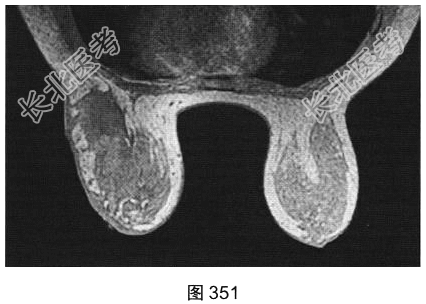

- [材料题] 患者女性,28岁,哺乳后3个月出现左乳肿胀、疼痛,患者无发热。既往体健。查体:左乳皮肤变红、皮温升高,外象限可触及一肿块。

- 简答题3、[提示]患者行乳腺MRI检查,如图351~图356所示。乳腺MRI检查的阳性影像学表现有?